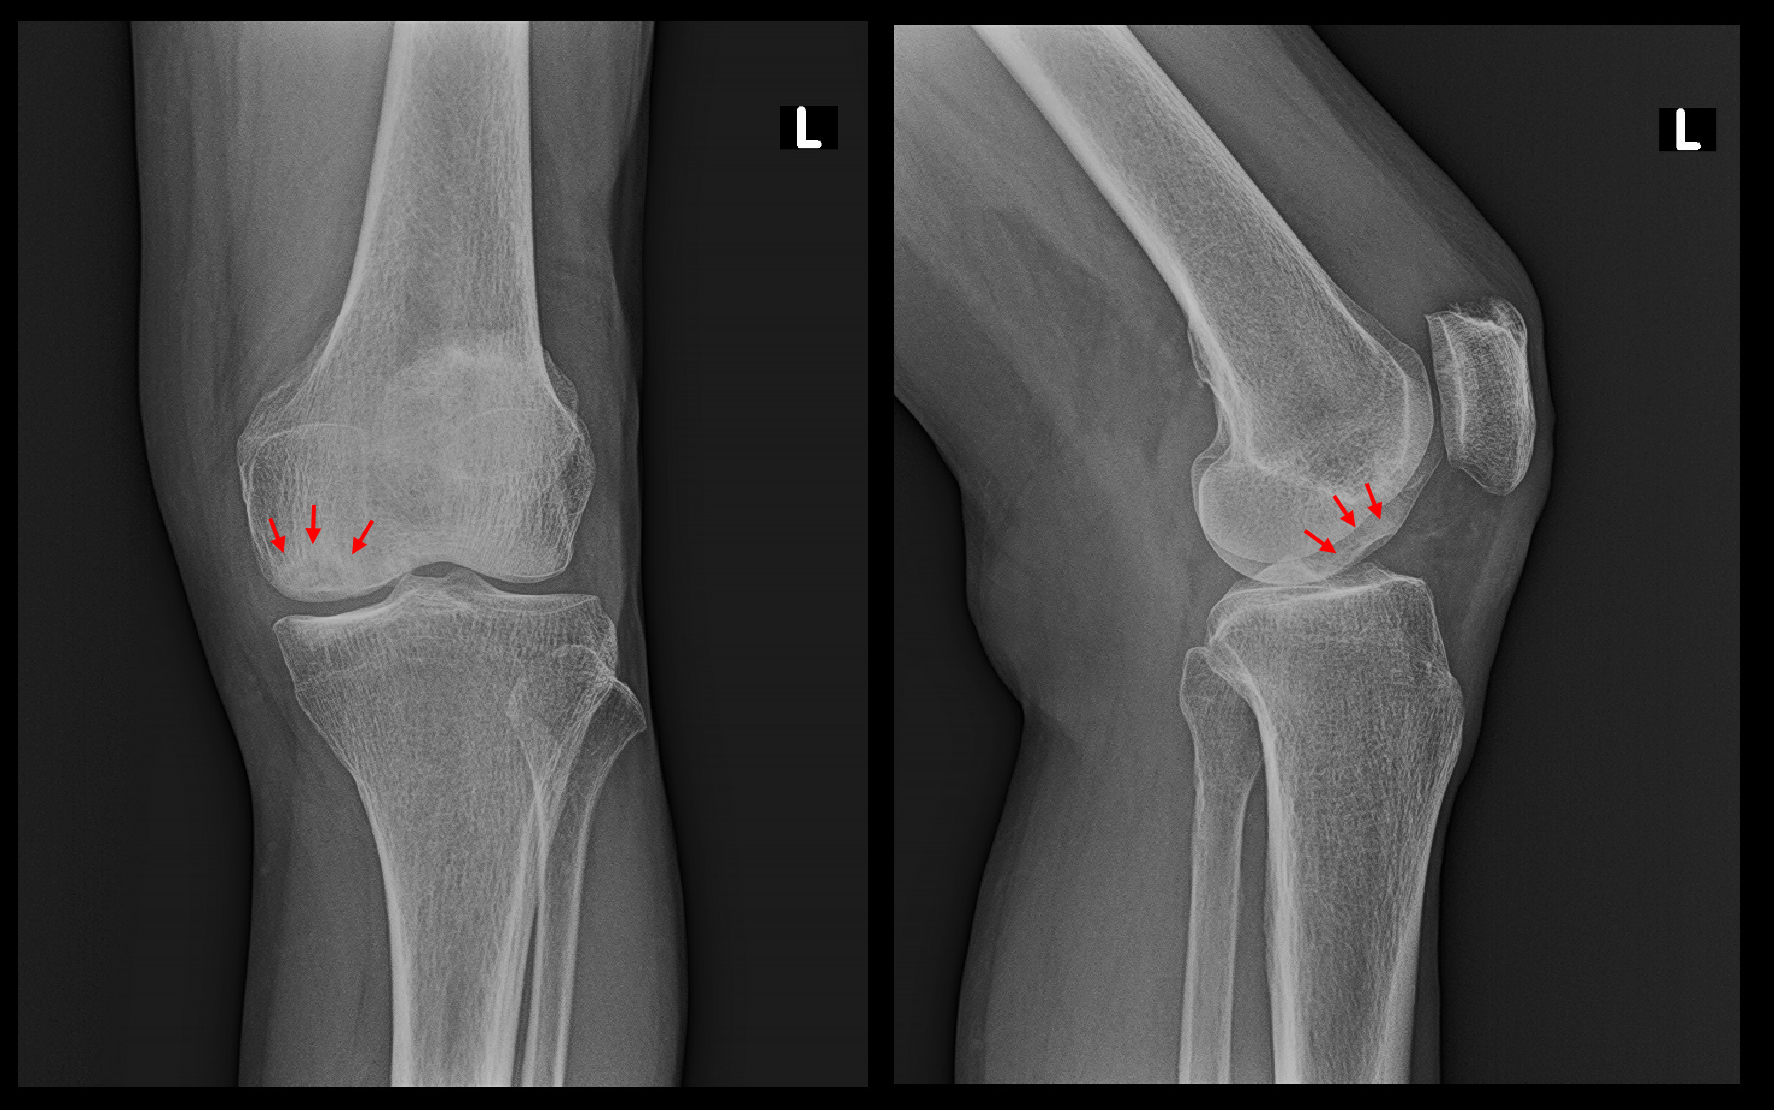

私の変形性膝関節症の治療方針では、関節裂隙(隙間)が消失してしまった重度の変形でなければ、人工関節は勧めていません。初診時のレントゲン像で関節裂隙は十分保たれていますから、この患者さんに人工関節を勧める考えはありませんでした。

令和3年3月6日のレントゲン像では関節裂隙は保たれており、陥凹した関節面の骨は再形成されて埋まってきていることが確認可能です。同年5月以降、患者さんの受診は終了しました。

当院では大腿骨内顆部の骨壊死となった患者さんであっても、関節裂隙が保たれていれば、大半の症例は手術を回避することができています。